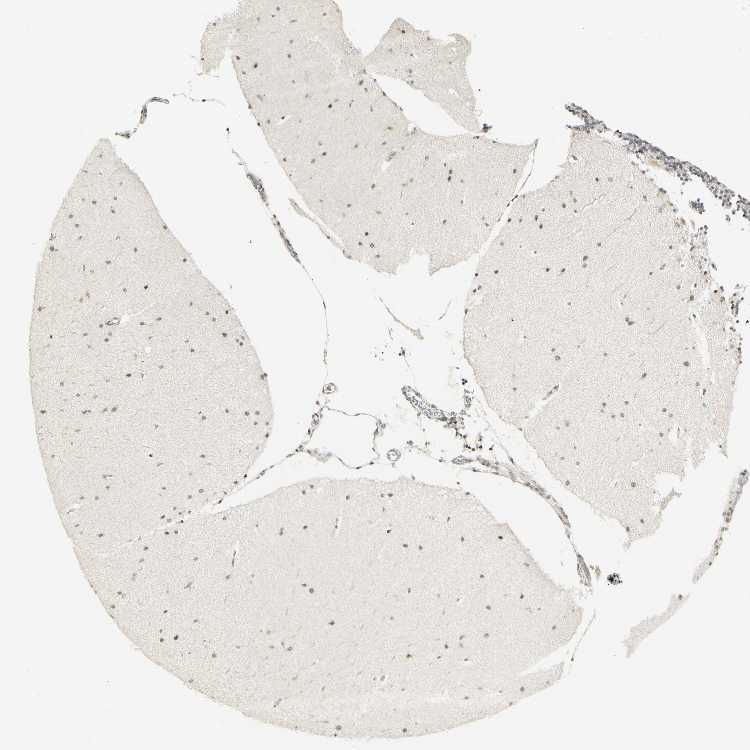

CEREBELLUM - Antibody stainingi

Antibody staining in the annotated cell types in the current human tissue is reported as not detected, low, medium, or high, based on conventional immunohistochemistry profiling in selected tissues. This score is based on the combination of the staining intensity and fraction of stained cells.

Each image is clickable and will lead to virtual microscopy that enables deeper exploration of all samples and also displays staining intensity scores, fraction scores and subcellular localization as well as patient and tissue information for each sample.

Antibody HPA006916Antibody HPA010568Antibody CAB017617

Purkinje cells MediumLowMedium

Cells in granular layer Not detectedNot detectedMedium

Cells in molecular layer LowNot detectedMedium